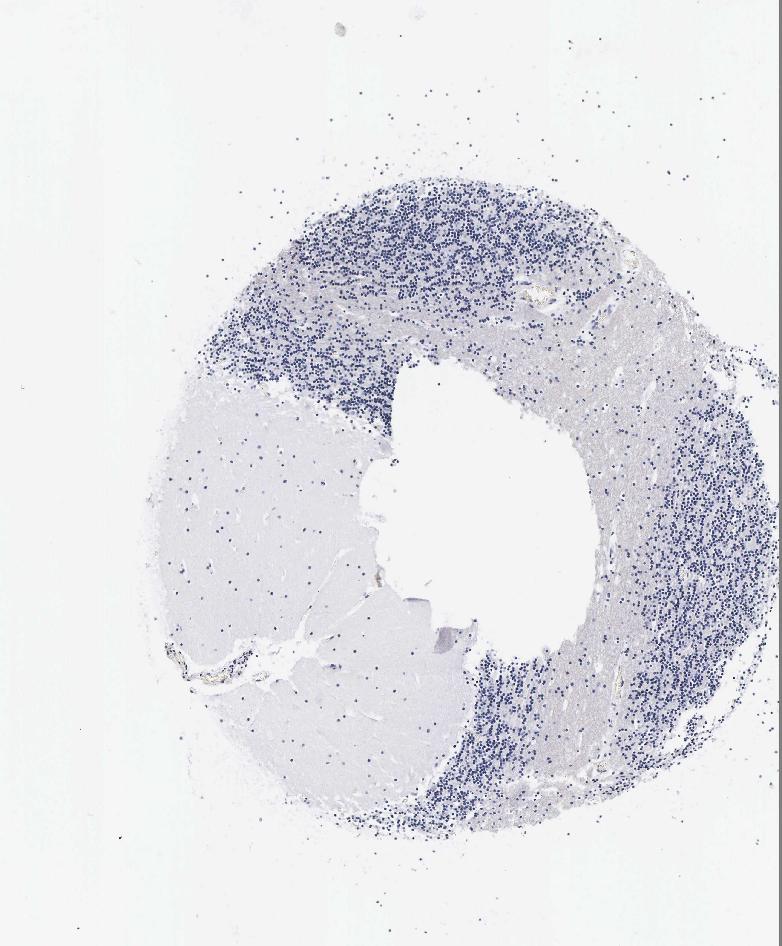

CEREBELLUM - Antibody stainingi

Antibody staining in the annotated cell types in the current human tissue is reported as not detected, low, medium, or high, based on conventional immunohistochemistry profiling in selected tissues. This score is based on the combination of the staining intensity and fraction of stained cells.

Each image is clickable and will lead to virtual microscopy that enables deeper exploration of all samples and also displays staining intensity scores, fraction scores and subcellular localization as well as patient and tissue information for each sample.

Antibody HPA001605Antibody CAB000008Antibody CAB000030

Purkinje cells Not detectedNot detectedNot detected

Cells in granular layer LowNot detectedNot detected

Cells in molecular layer LowNot detectedNot detected